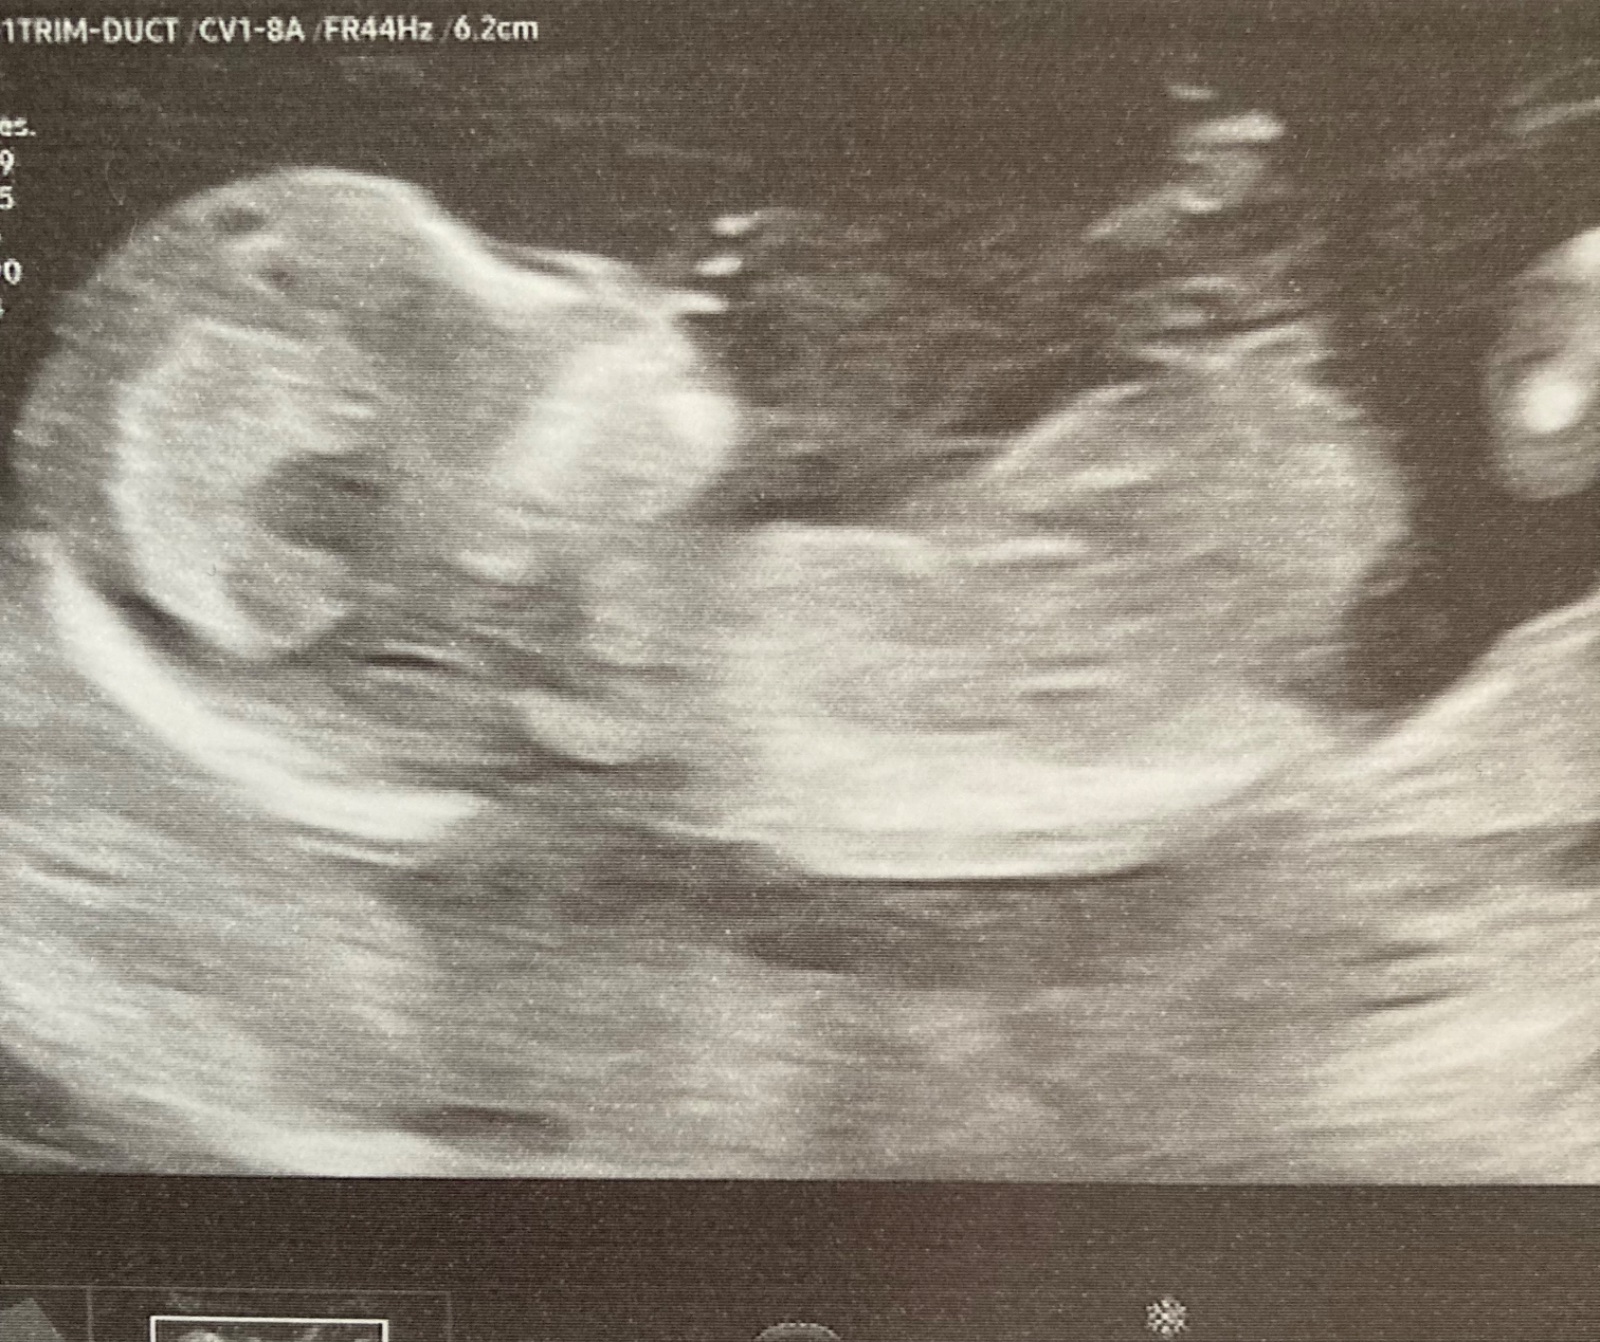

Ultrazvuk 12. tt. Zdá se skutečně poznat podle pahorku pohlaví plodu?

prosím o informaci, zda se skutečně dá poznat podle pahorku pohlaví plodu.

bohužel, z této fotografie nic poznat nelze. ☹